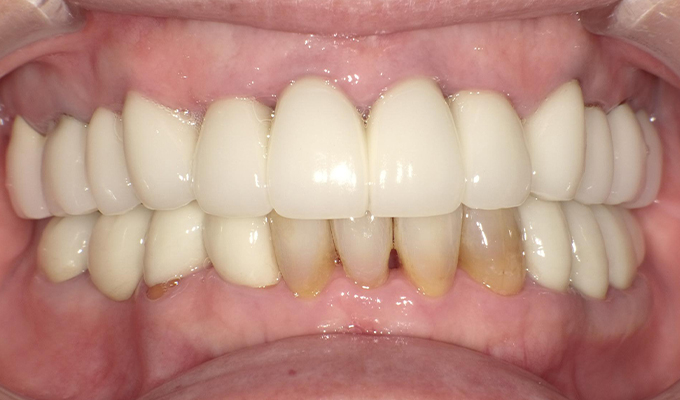

case2ジルコニアクラウンの症例

初診時(2013年)

初回メンテナンス時(2014年)

最新メンテナンス時(2024年)

- 初診時の年齢

- 50代女性(2013年)

- 主訴

- 右上奥の銀歯が取れた。この際悪いところはすべて治療したい。

- 治療内容

- 取れてしまった銀歯の根が割れていたため抜歯しブリッジの治療になりました。

「せっかくならきれいにしたい」と八重歯になっている右上下の犬歯を抜きジルコニアブリッジを入れました。

セルフケアもしっかりやっていただいているので10年経過してもきれいな状態を維持されています。